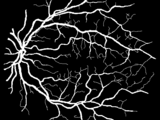

We propose a filter that selectively responds to vessels and that we call B-COSFIRE with B standing for bar which is an abstraction for a vessel. It is based on the existing COSFIRE (Combination Of Shifted Filter Responses) approach.

A B-COSFIRE filter achieves orientation selectivity by computing the weighted geometric mean of the output of a pool of Difference-of-Gaussians filters, whose supports are aligned in a collinear manner. It achieves rotation invariance efficiently by simple shifting operations.

The proposed filter is versatile as its selectivity is determined from any given vessel-like prototype pattern in an automatic configuration process. We configure two B-COSFIRE filters, namely symmetric and asymmetric, that are selective for bars and bar-endings, respectively. We achieve vessel segmentation by summing up the responses of the two rotation-invariant B-COSFIRE filters followed by thresholding.

- blood vessels in medical images